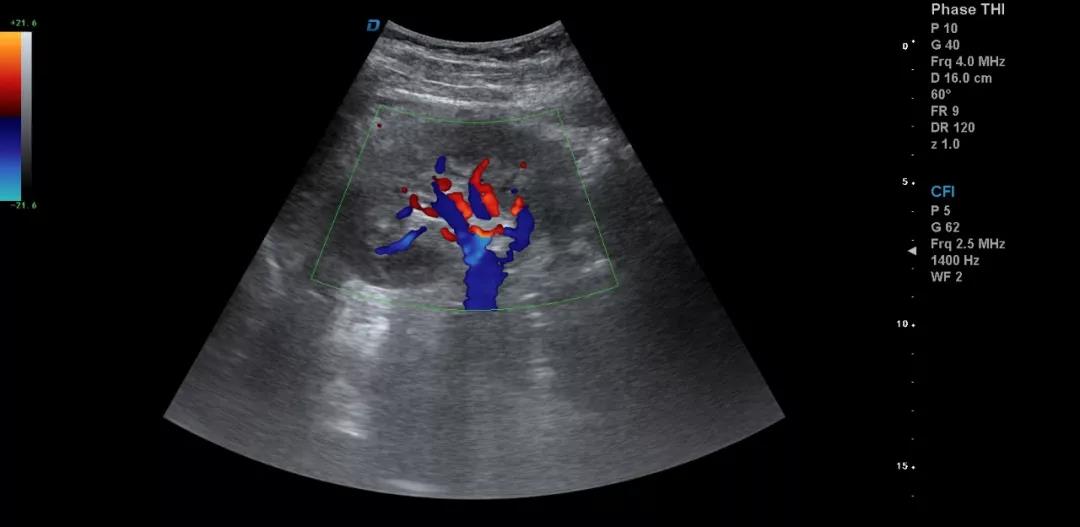

3.注意在工作中積累超聲資料

典型圖片、經典病例圖片、動態影像資料積累的多了分析總結之后就提高了。疑難病例資料積累后,可以隨訪病人,然后總結得到的臨床資料和病理結果。

有了手術結果和病理才會有真正的提高。按器官、按系統、按學科進行總結每一個、每一類疾病正常及異常圖片就是知識的積累。